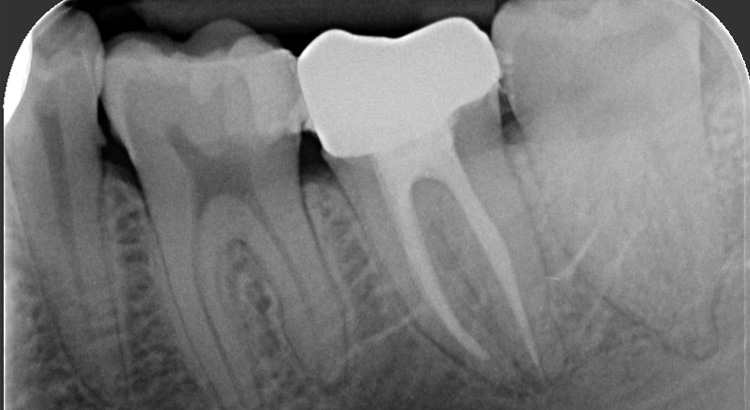

Protesi fissa su denti naturali

Il paziente presentava carie su tutti e tre gli elementi del settore posteriore, fondamentali per una corretta masticazione. La carie aveva portato ad una grave compromissione degli elementi, dolore dentale e il paziente masticava solo dall’altro lato. Grazie al trattamento endodontico e l’utilizzo delle nuove ceramiche è stato possibile ristabilire l’estetica e soprattutto la funzione masticatoria di quel lato.